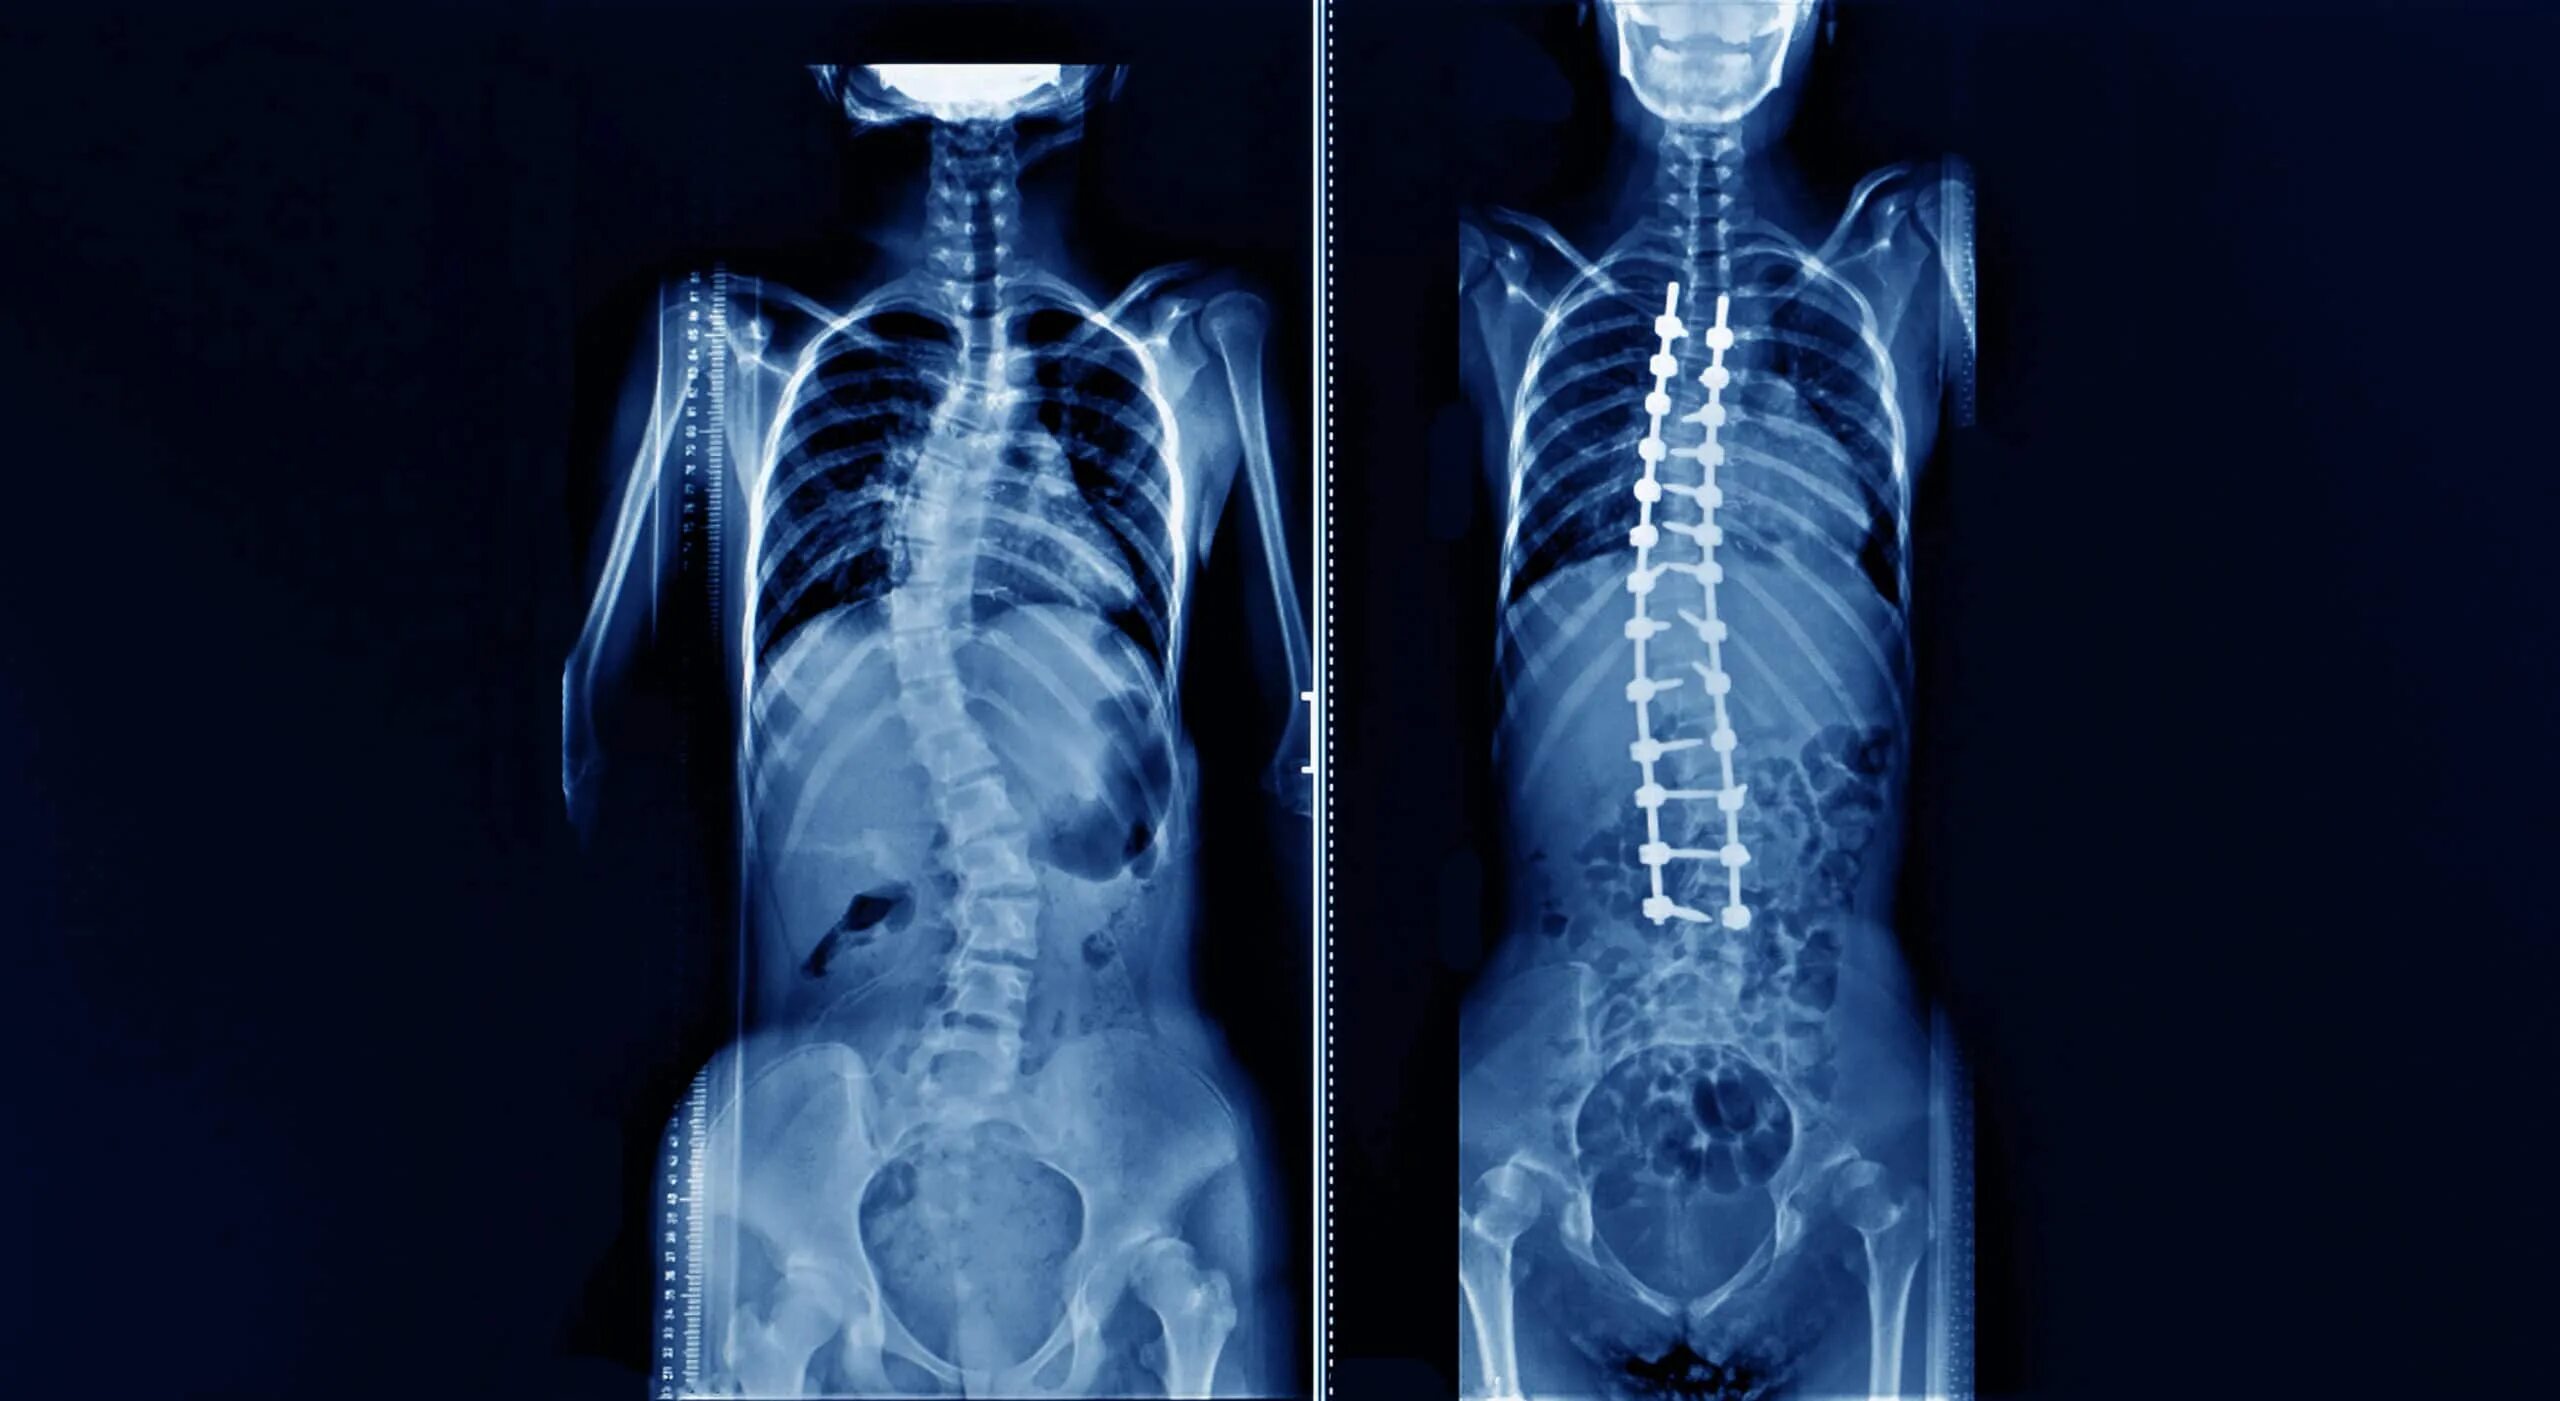

Синдром прямой